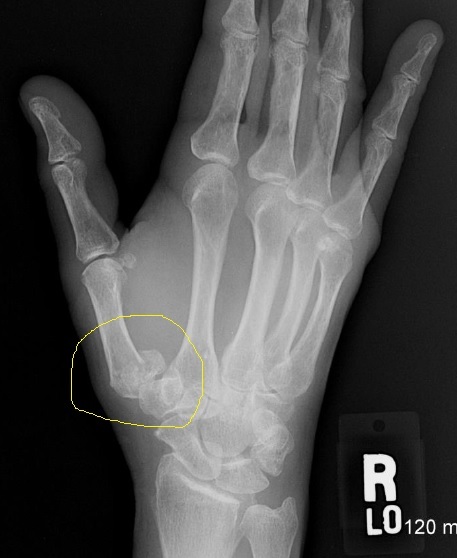

Identify

Rolando fracture

(base of the 1st metacarpal @ CMC joint)